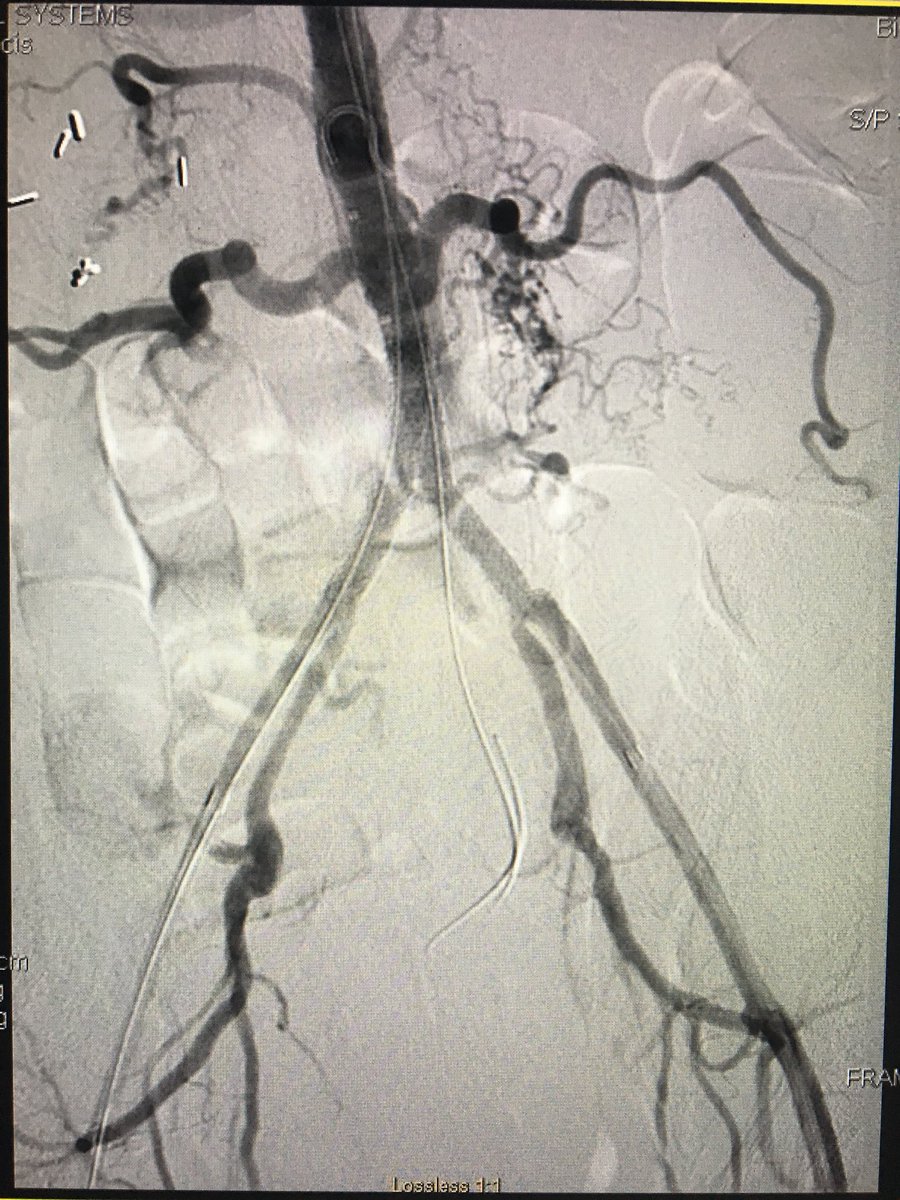

Chronically occluded distal aorta & b/l common iliac arteries. Subintimal arterial flossing w/ antegrade-retrograde intervention (SAFARI), recan, & distal aorta + b/l kissing stents in b/l common iliac arteries. SIR RFS Society of Interventional Radiology JVIR #TwittIR #IRad

Chronically occluded distal aorta &amp; b/l common iliac arteries. Subintimal arterial flossing w/ antegrade-retrograde intervention (SAFARI), recan, &amp; distal aorta + b/l kissing stents in b/l common iliac arteries. <a href="/SIRRFS/">SIR RFS</a> <a href="/SIRspecialists/">Society of Interventional Radiology</a> <a href="/JVIRmedia/">JVIR</a> #TwittIR #IRad